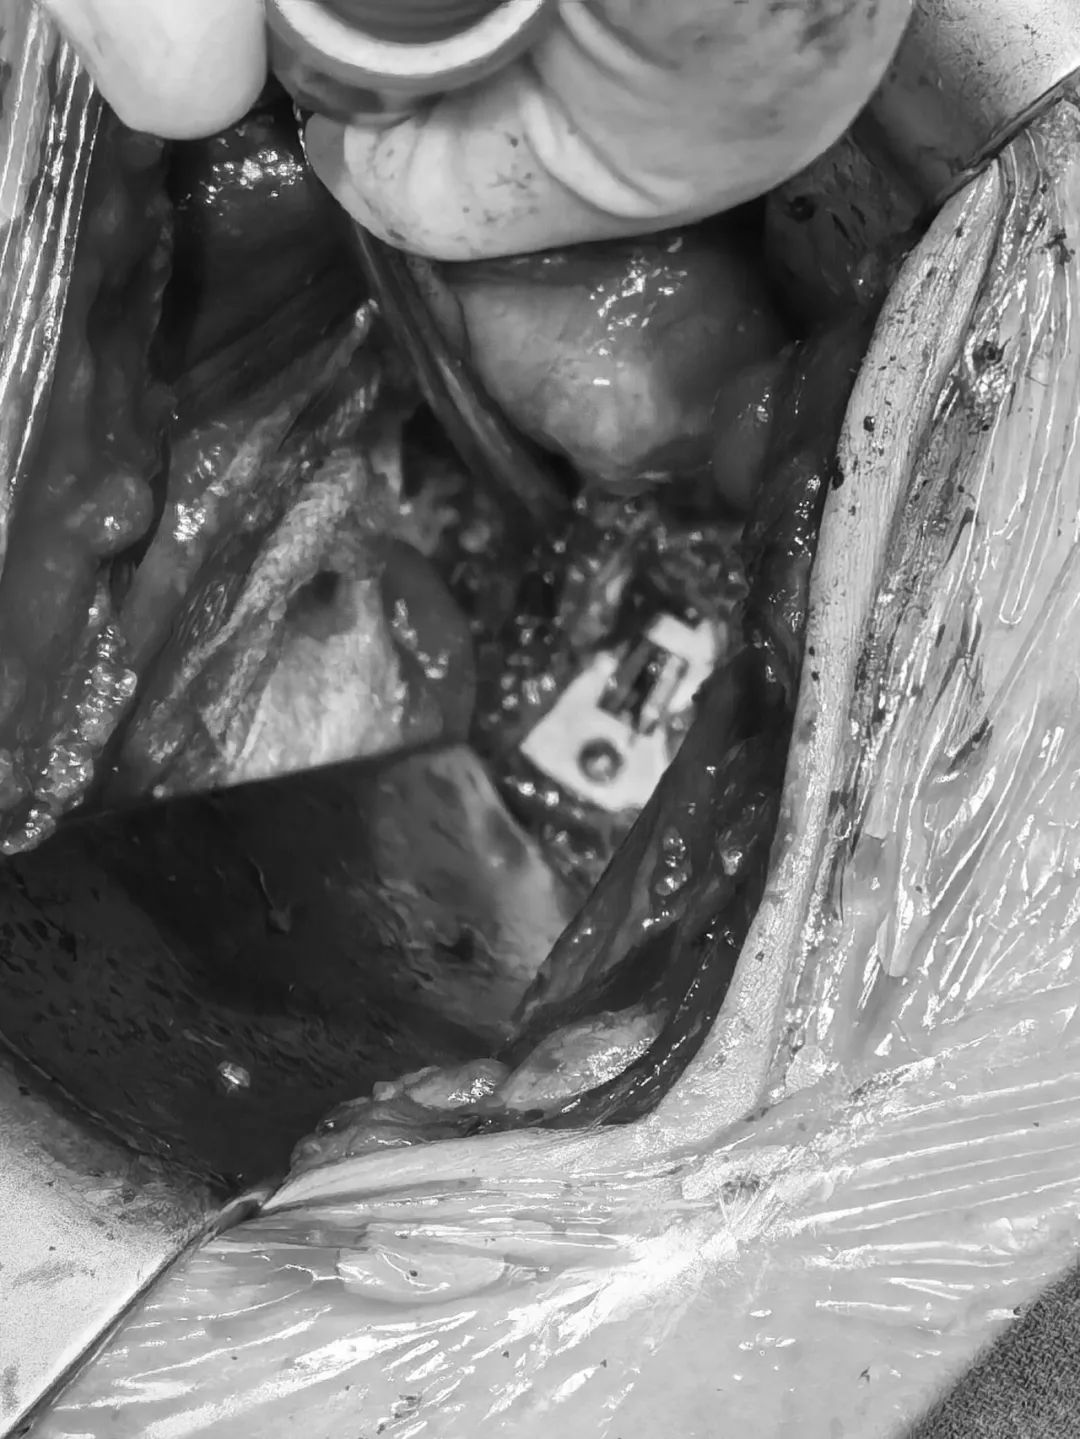

參考“固定夾選用指示牌”,選擇合適的固定夾型號

固定夾植入(考慮患者長期不融合,可能存在終板硬化。因此,先使用固定夾開路器預(yù)開路,再植入固定夾)

直視圖:cage與固定夾完全打入后